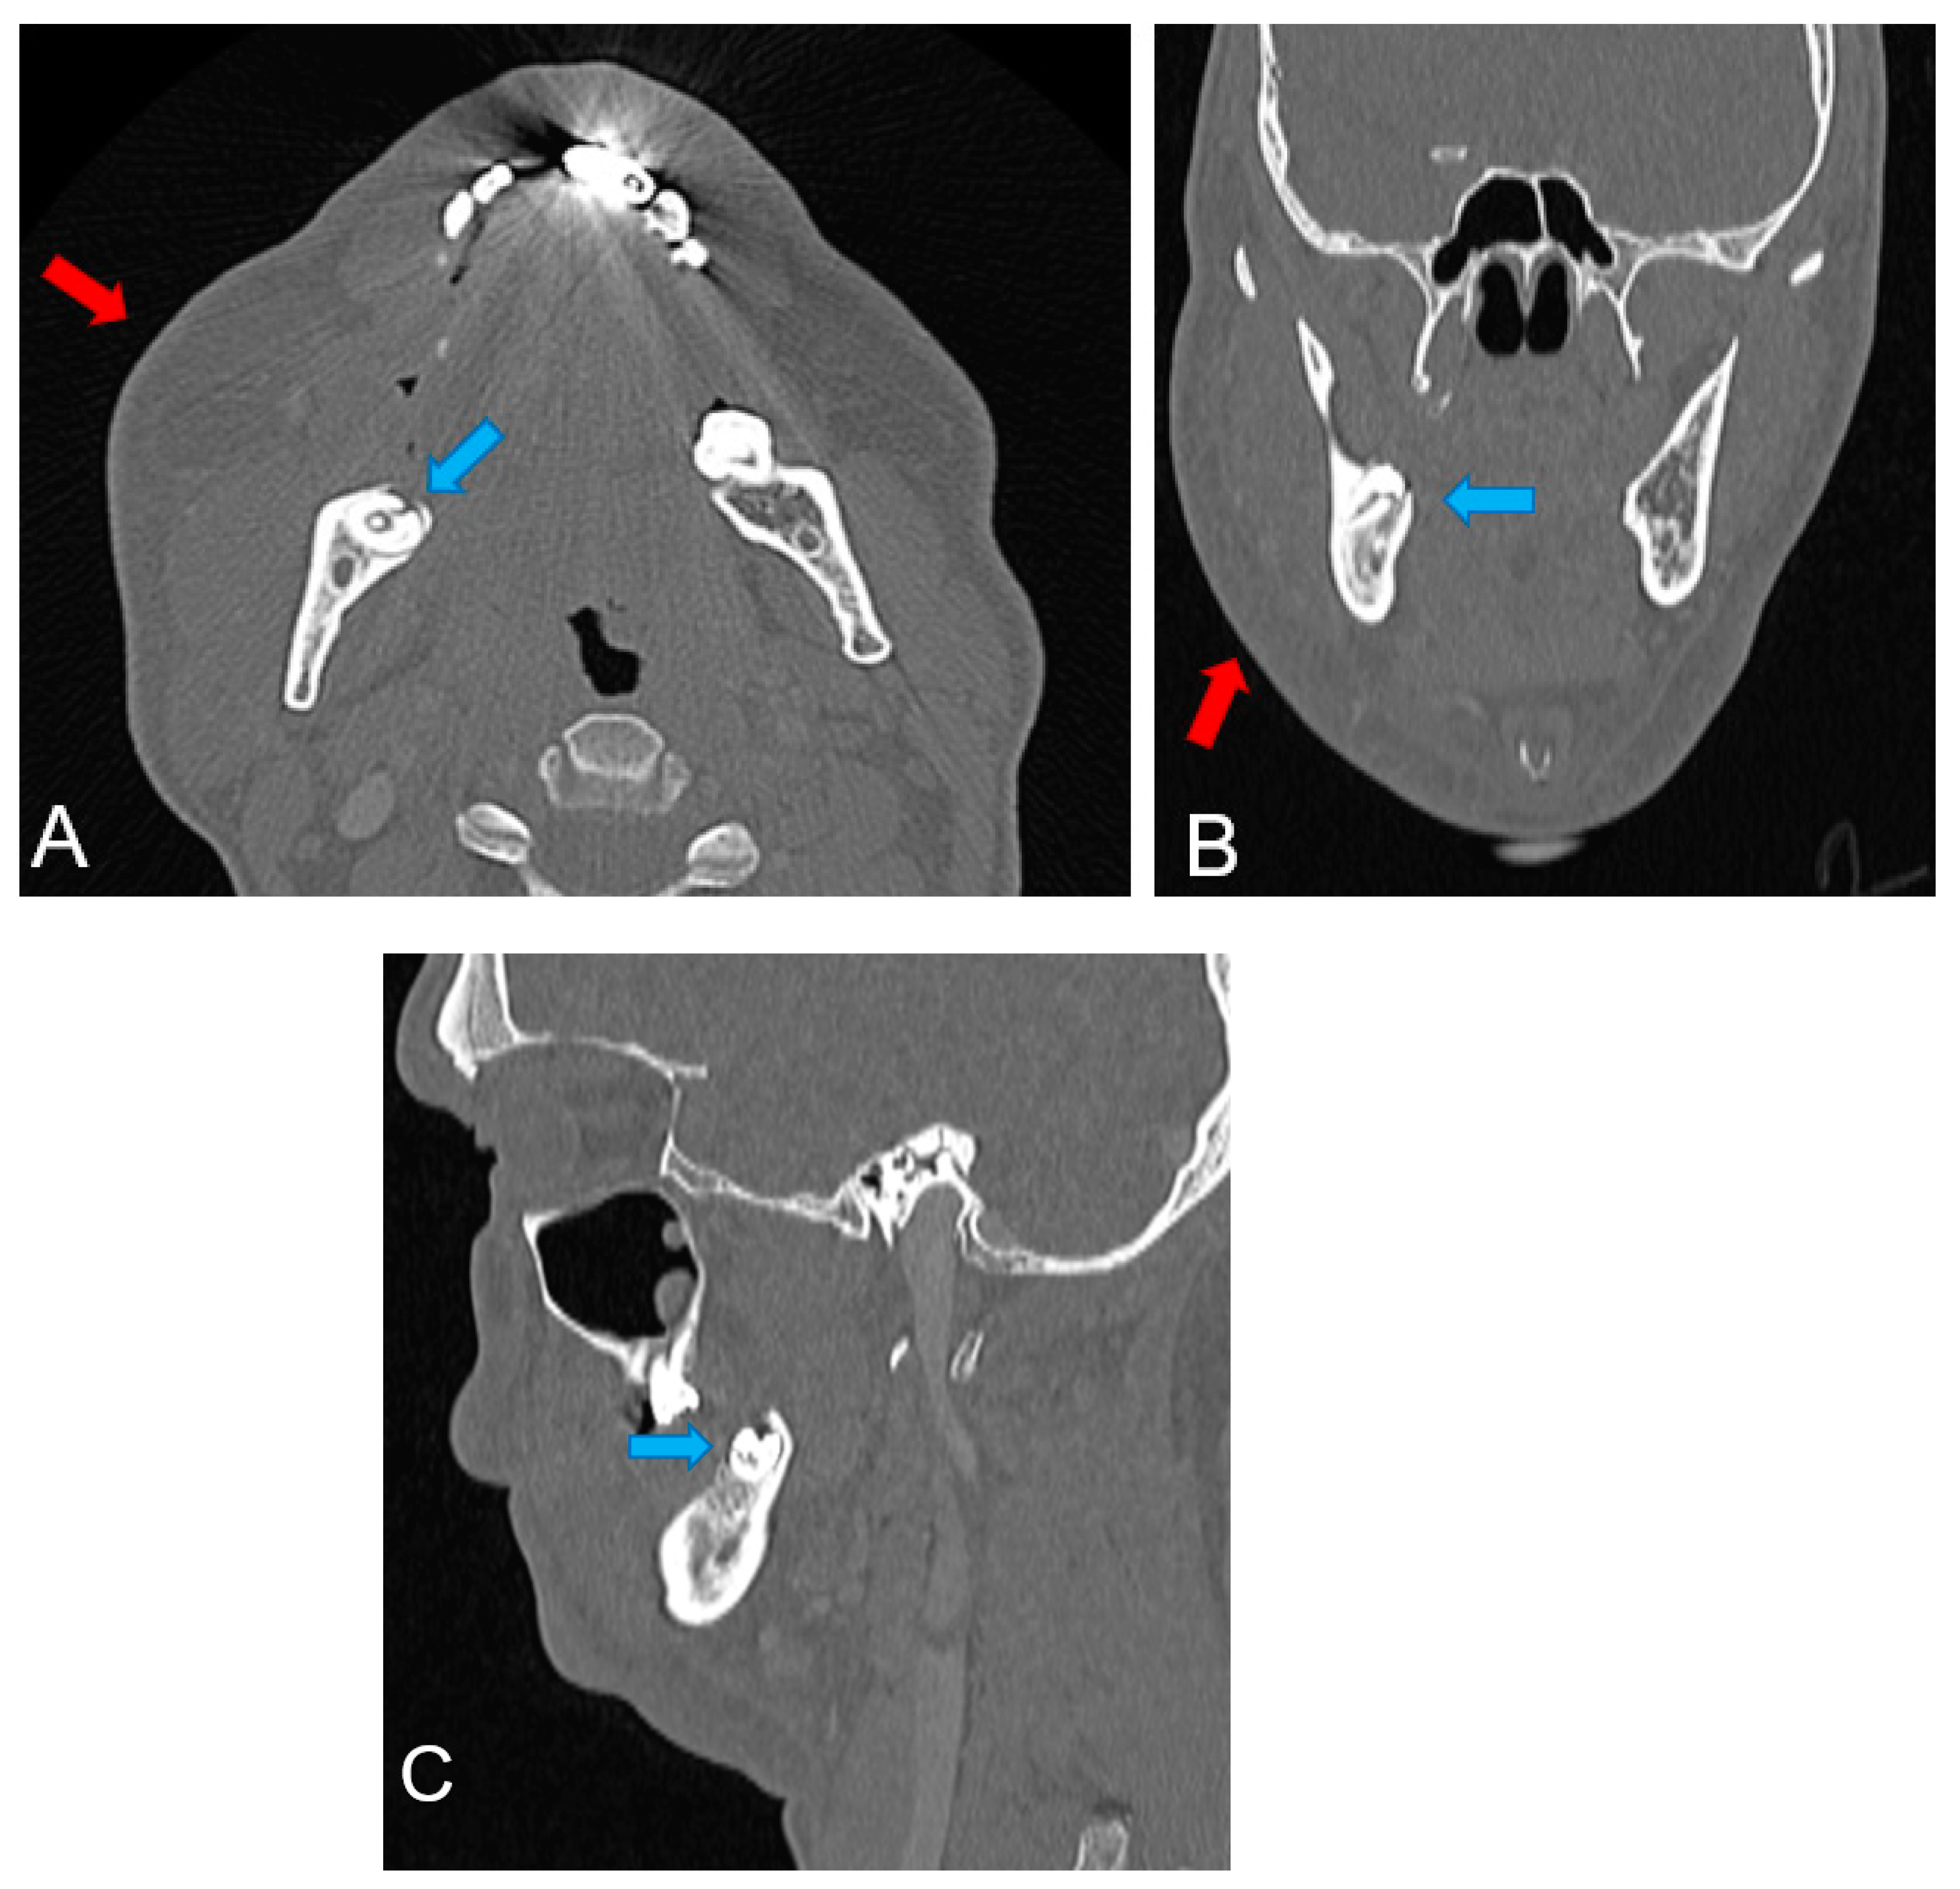

To investigate a possible fracture of the mandible, a computed tomography (CT scan) examination was performed (Figure 3). It revealed right maxillary and mandibular subcutaneous swelling and infiltration, with thickening of the fascia and masseter muscle, without purulent collections. The CT scan revealed no fractures of the mandibular horizontal ramus. A diagnosis of cellulitis was made.

Figure 3.

CT scan examination: (A) axial view; (B) frontal view; (C) sagittal view. The red arrow in (A,B) indicates the facial cellulitis lesion and the blue arrow in (A–C) the coronal fracture of the impacted lower right wisdom tooth.